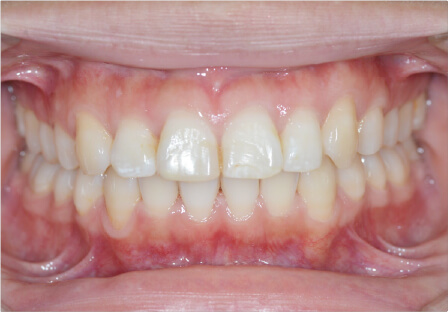

過蓋咬合の症例

6歳

/

男性

相談内容

歯がガタガタ・鼻づまり・口呼吸

カウンセリング・診断結果

治療内容・方法

全顎アライナー矯正・拡大装置

術後の経過・現在の様子

上下リンガルアーチ

治療のリスク

痛み・歯根吸収・歯肉退縮・虫歯・後戻り

費用・治療期間

140,800円、1年6ヶ月